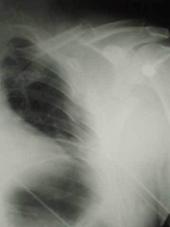

TRAUMATISME TORACICE

Emfizem subcutanat

Emfizem subcutanat Emfizem subcutanat

Aspect radiologic Imagine CT